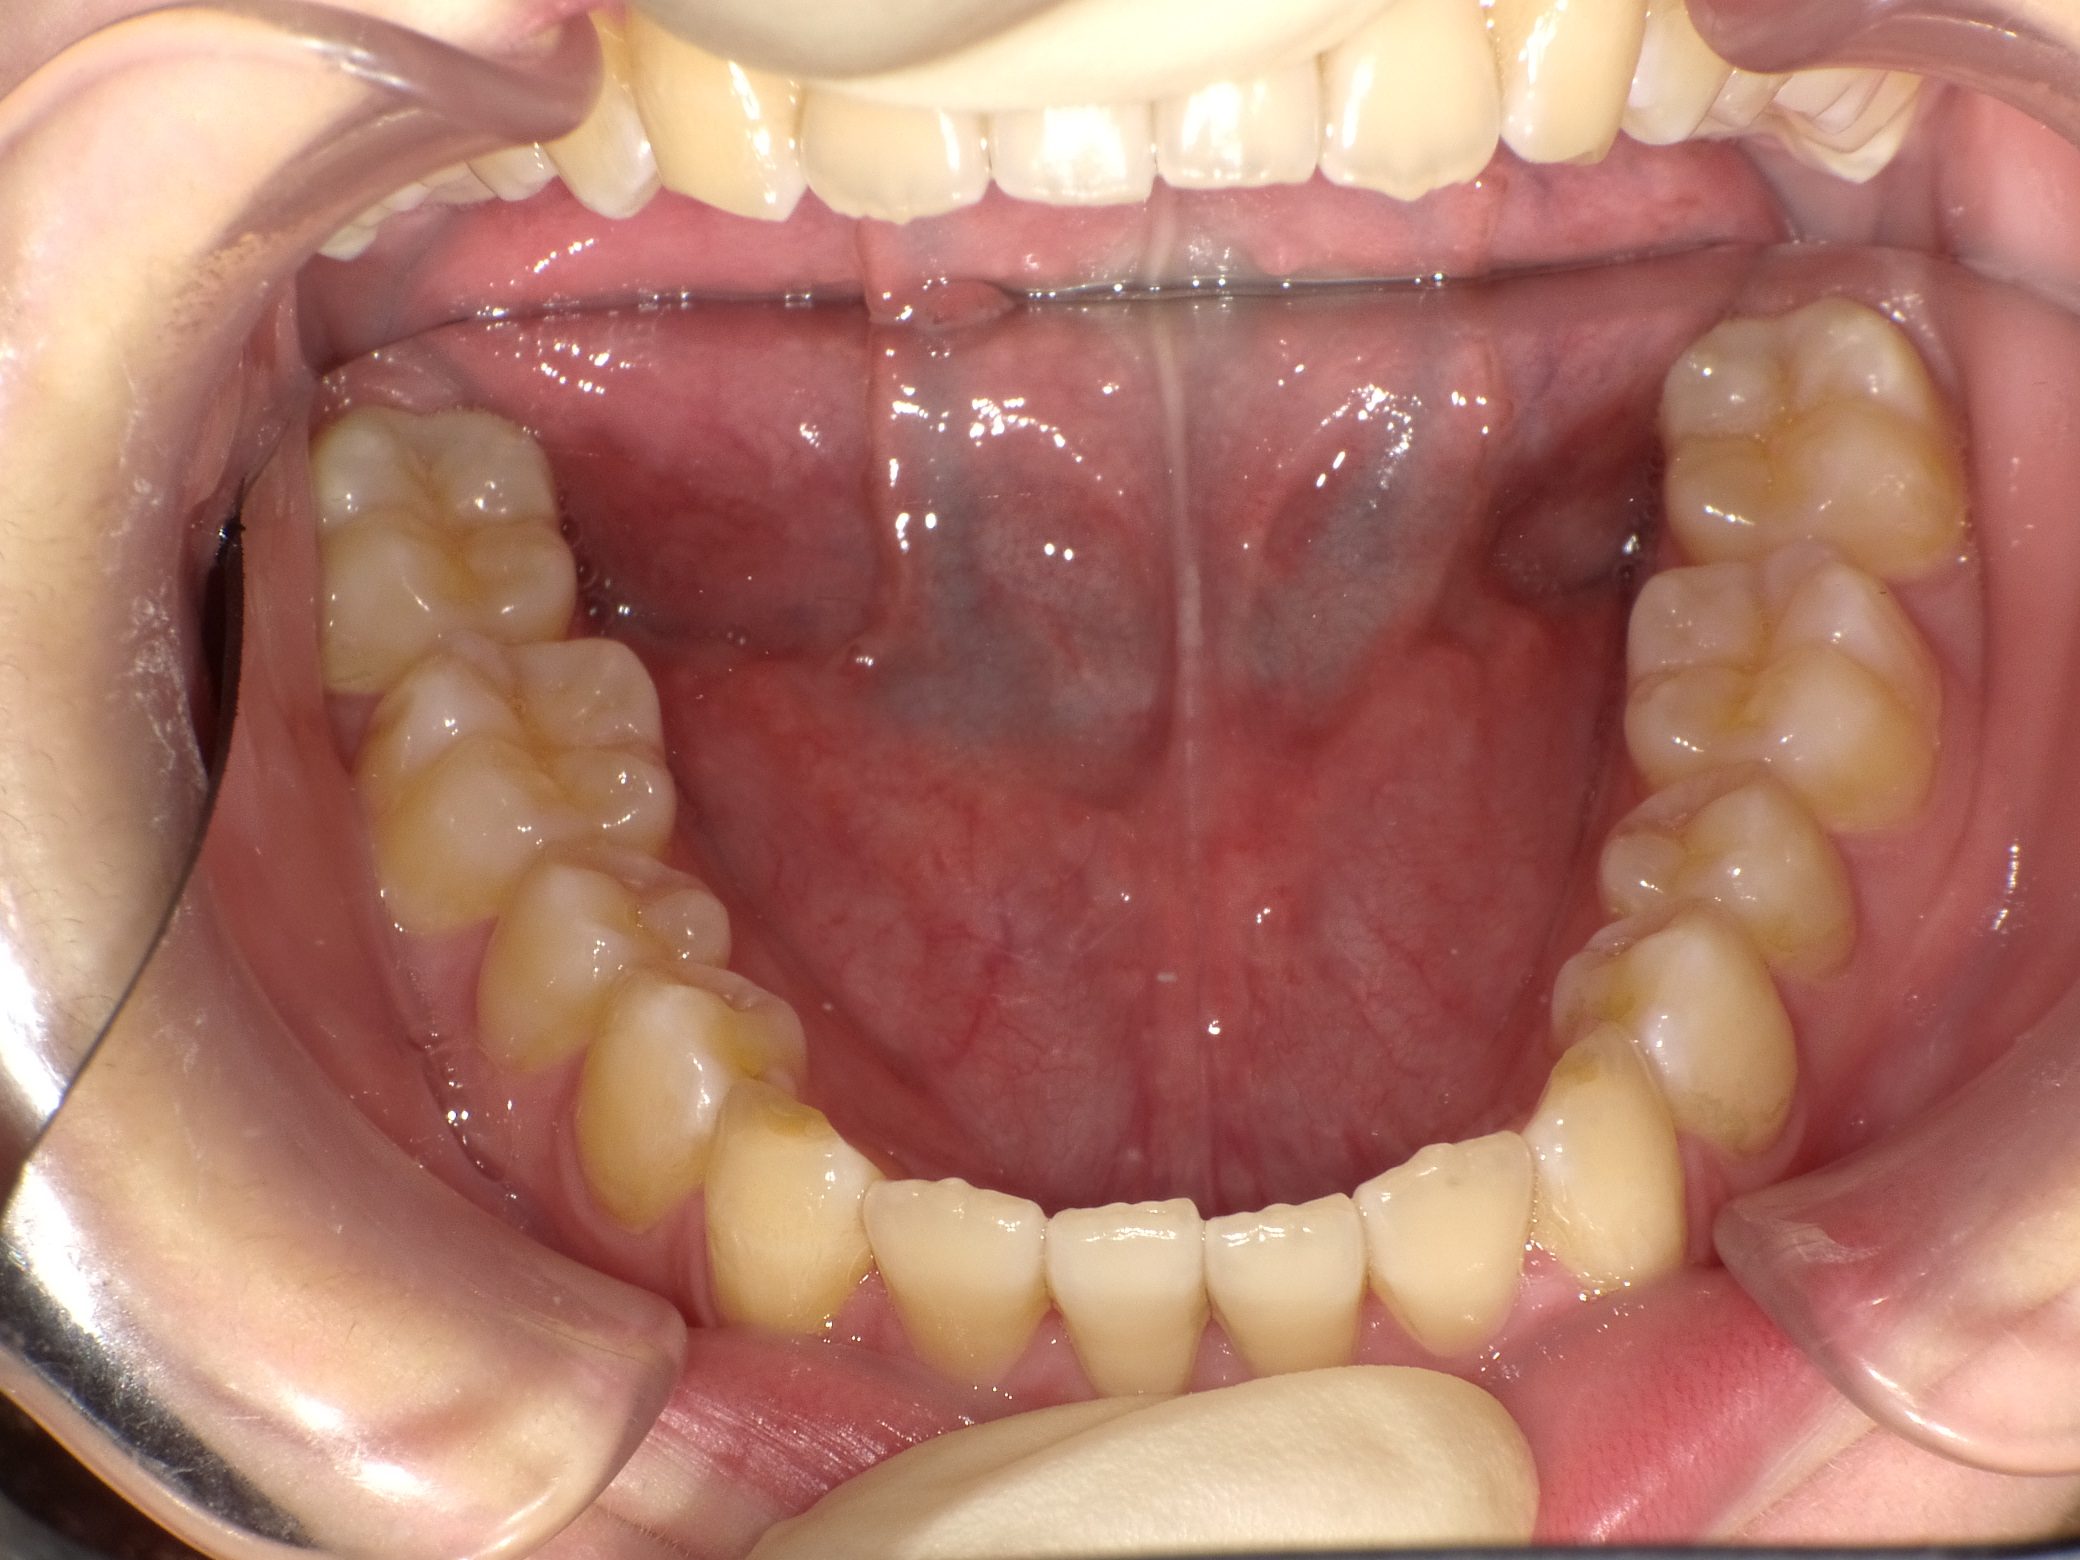

Before

After

【中学生】インビザライン矯正 叢生(ガタガタ)と上顎前突(出っ歯)を改善

でこぼこ

出っ歯

非抜歯

2期治療のみ

途中 留学などあり、装置(アライナー)を全部持って行ってもらう といった時期がありましたが、

装置(アライナー)が浮くこともなく しっかり進めてくれたので 1年4カ月で終了しました。